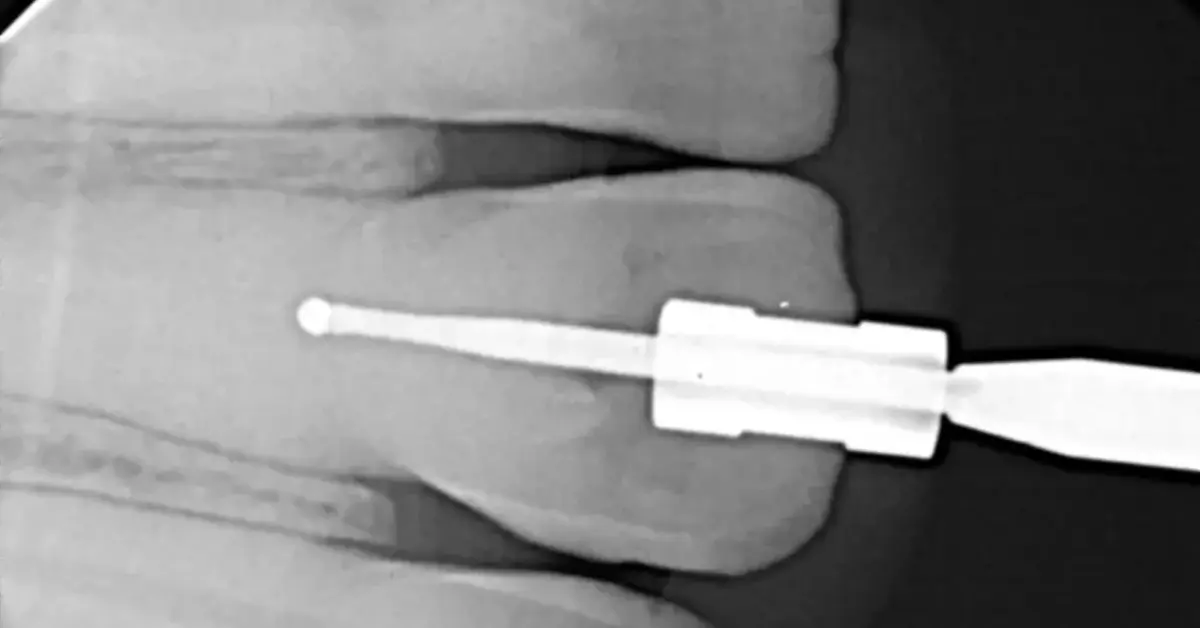

This guided endodontics in chennai case study shows precise, minimally invasive treatment with fast recovery for young patients at Kidz N Teenz Chennai.